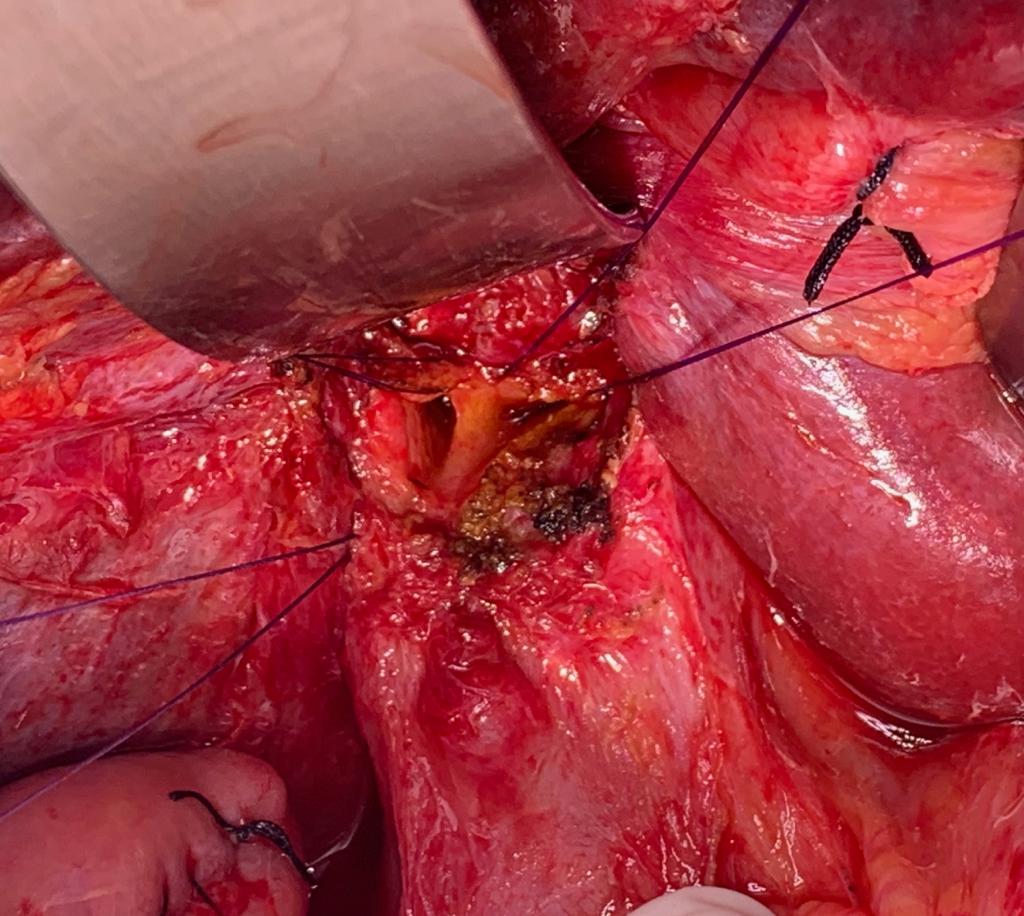

A Challenging Scenario: 40-year-old male with idiopathic chronic pancreatitis with intractable pain and sitophobia

40 year old male with idiopathic chronic pancreatitis presented with intractable pain, sitophobia with severe weight loss (adult male weighs 29 Kg) and history of recurrent episodes of GI bleed. He also has CKD (cr1.7) related to neurogenic bladder. Patient was shifted to us in shock with HB 3 gm % and massive GI bleed. MRI and CT angio showed a large 6x5 cm Pseudoaneurysm in uncinate process of pancreas probably arising from inferior pancreaticoduordenal artery causing hemosuccus pancreas. In view of CKD we chose to tackle aneurysm by direct glue embolisation of aneurysm sac to avoid the high volume contrast of conventional angio (image) Pt was put on NJ feeds in view of severe malnutrition secondary to intractable pain and sitophobia. Post embolisation 2 months later he came back with weight gain of 8 kg and a stable Hb%. His Repeated CT scan showed a persistent intrapancreatic head cyst with dilated pd in body and tail. The aneurysm cavity filled with glue cast has shrunk to almost one fifth the initial size. In view of large duct disease with Pseudoaneurysm we decided to go ahead with a whipple pancreaticoduodenectomy. The post op specimen shows the intrapancreatic cyst and the glue cast of the aneurysm (yellow arrow). His recovery was uneventful and is completely pain free post procedure.